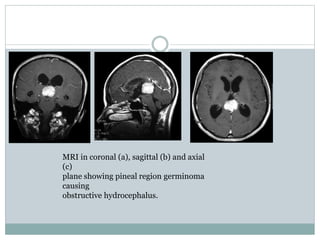

MRI in coronal (a), sagittal (b) and axial

(c)

plane showing pineal region germinoma

causing

obstructive hydrocephalus.